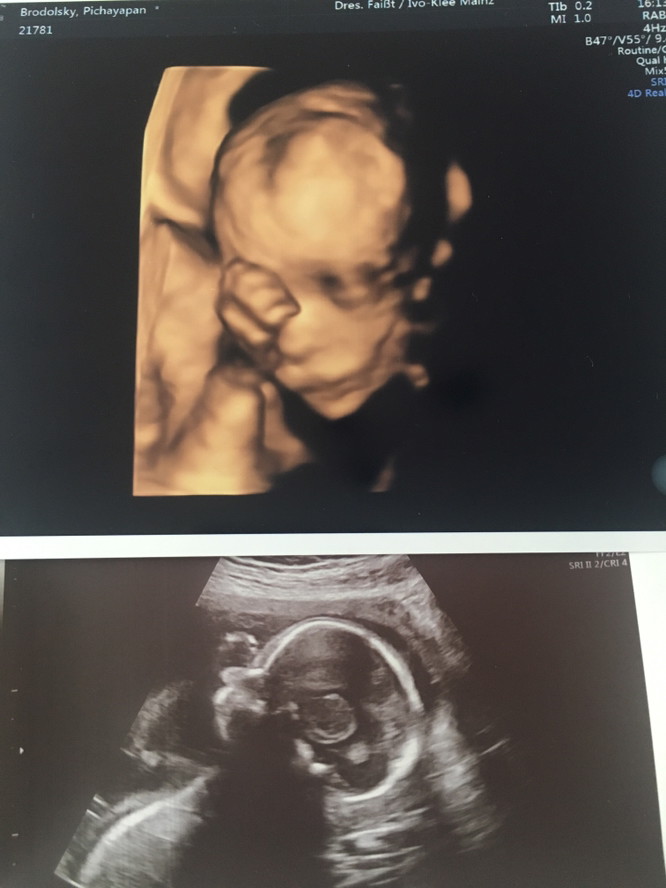

21weekคะ ผู้ชาย

ซาวตอน 23W คะ